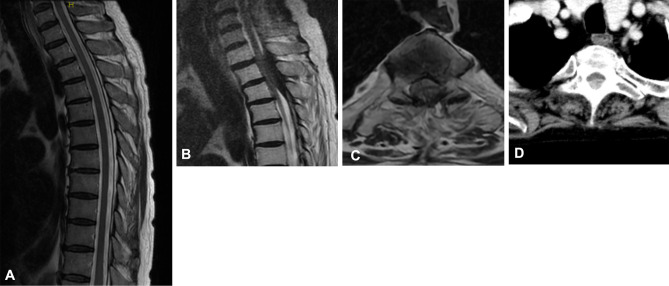

Hypertrophic Spinal Pachymeningitis in a Patient with Chronic Antineutrophil Cytoplasmic Antibody-Associated Nephritis: A Case Report.